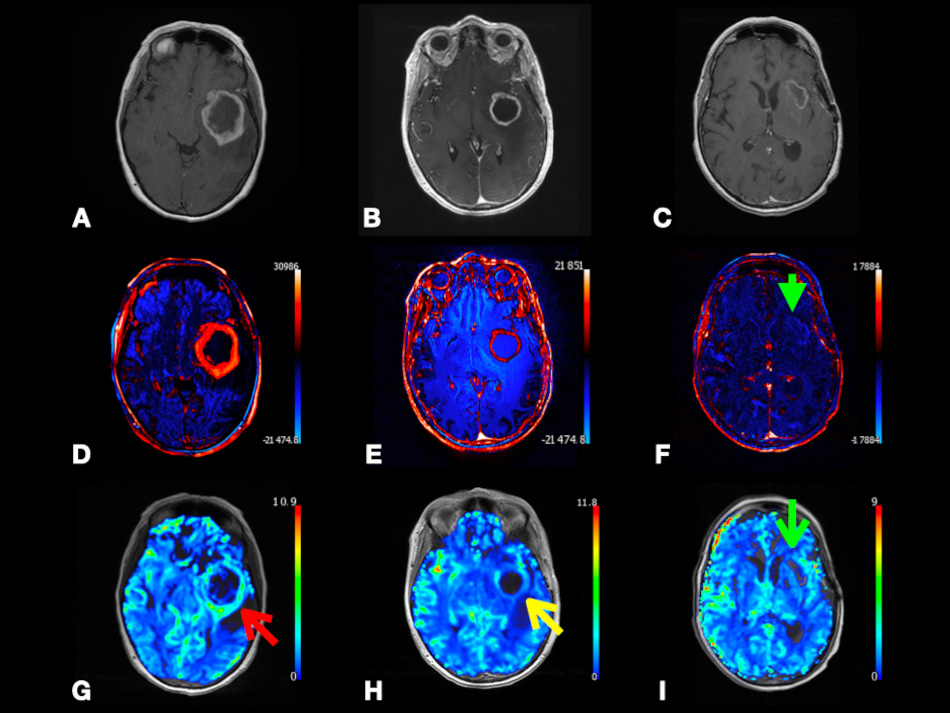

In Fig. 7, we present a case of left temporal lobe GBM (WHO Grade 4) with false-positive perfusion imaging for recurrence. Using DSC, baseline images showed peripheral hyperperfusion. Four months later after the surgery, images showed enhancement and hyperperfusion concerning for recurrence; the patient underwent subsequent resection with no tumor on pathology. This case shows that using color-coded rCBV maps can be misleading as both tumor recurrence and pseudoprogression may show relatively increased perfusion. However, as we discussed in the earlier paragraph, CBV is found to be significantly higher in GBM recurrence compared to pseudoprogression. This highlights the importance of having more studies comparing CBV between pseudoprogression versus recurrence to define a specific CBV value or threshold that can be associated with GBM recurrence. Calculating the specificity and sensitivity of this CBV value is also encouraged. This also highlights the importance of using quantitative parameters, such as tumoral and peritumoral CBV and CBF to compare between GBM and MTs as depending on observing hyperperfusion signals on the color-coded maps is subjective and can be misleading.

Fig. 7.Left temporal lobe glioblastoma (WHO Grade 4) with false-positive perfusion imaging for recurrence and subsequent treatment-mediated response. Axial post-contrast T1-weighted (A–C), color-coded subtraction maps (D–F), and color-coded rCBV maps (G–I) from DSC data. Baseline images (A,D,G) depicting enhancing mass with central necrosis and peripheral hyperperfusion (red arrow). Images obtained four months later (B,E,H) depicting enhancement and hyperperfusion (yellow arrow) concerning for recurrence; subsequent redo resection with treatment effect and no tumor on pathology. Images obtained eight months later (C,F,I) after temozolomide and Avastin depicting T1 shortening, resolved enhancement (green arrowhead), and resolved hyperperfusion (green arrow) at the superior margin of the expanded resection cavity compatible with treatment response. Abbreviations: rCBV, relative cerebral blood volume; DSC, Dynamic susceptibility contrast MRI.